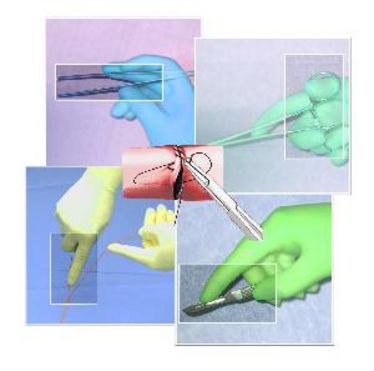

BASIC SURGICAL SKILLS - Gefäßnaht

BASIC SURGICAL SKILLS - Gefäßnaht